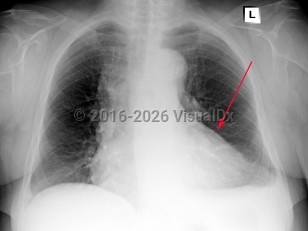

Pneumothorax

Spontaneous pneumothoraxSpontaneous pneumothorax